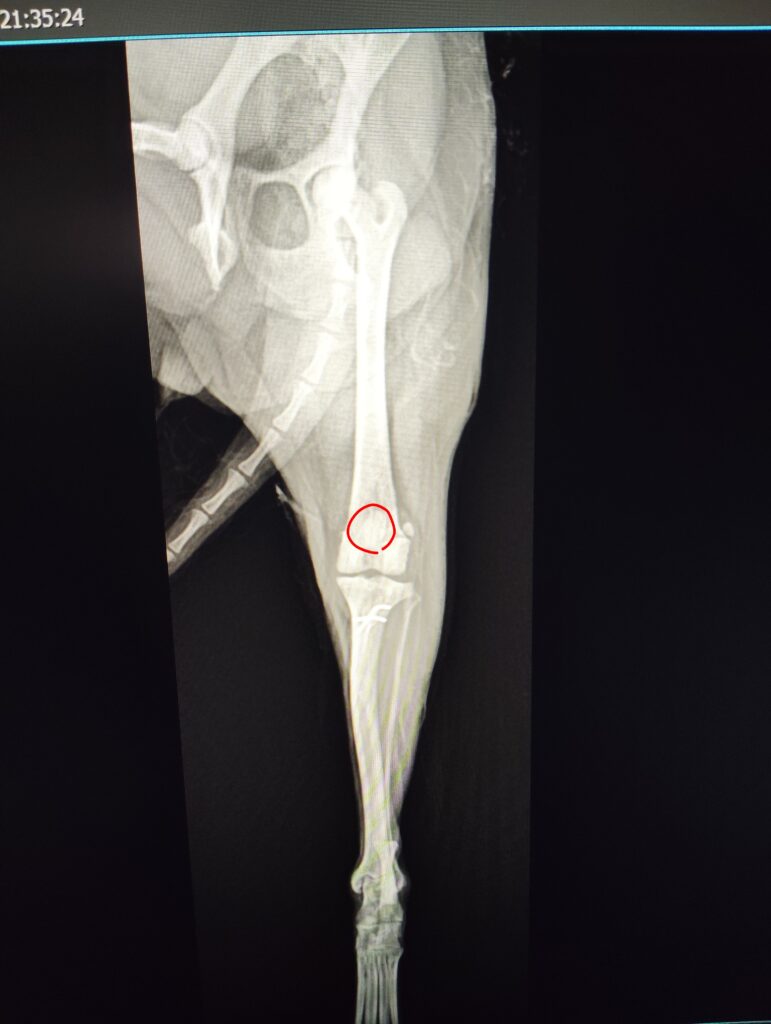

【レントゲン検査】

・左膝蓋骨内方に偏位